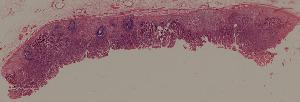

49.梅毒性主动脉炎

50.大叶性肺炎

51.肺肉质变

52.小叶性肺炎

57.肺癌

59.慢性萎缩性胃炎

60.胃溃疡

61.胃腺癌(胃粘液腺癌)

62.急性普通型病毒性肝炎

63.慢性活动性肝炎

64.急性重型病毒性肝炎

65.亚急性重型病毒性肝炎

66.活动性结节性肝硬化

67.非活动性结节性肝硬化

68.胆汁性肝硬化

69.肝细胞性肝癌

72.膜性肾小球肾炎

73.急性肾小球肾炎

74.新月体性肾炎

75.慢性硬化性肾小球肾炎